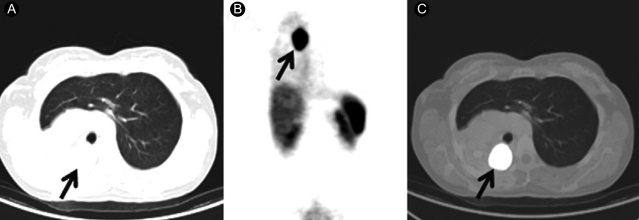

In the present study, all the patients presented with a primary tumor. There was significant uptake of 68Ga-DOTATOC in 19/20 patients (detection rate of 95%), and these findings corroborated the diagnosis of carcinoid. The findings for a typical positive case are shown in Fig. 1. Case 5 had symptoms of Cushing's syndrome. CT demonstrated a small, suspicious-looking lesion in the left lower lobar parenchyma, but the finding was not conclusive. Obtaining a biopsy was not possible owing to the small size of the lesion. 68Ga-DOTATOC uptake by the lesion was high, supporting the diagnosis. Excision of the lesion resulted in a complete clinical response for this patient. The results obtained with CECT and 68Ga-DOTATOC PET/CT were concordant with respect to the primary lesions. CECT did not reveal any lesions other that the primary tumor in any of the patients. 68Ga-DOTATOC PET/CT detected additional lesions in case 15 (Fig. 2) and facilitated tumor staging, prognostication, and decisions as to the choice of treatment offered to this patient. The tumor, which did not show any significant uptake of 68Ga-DOTATOC, was defined as an atypical carcinoid (case 18). Atypical carcinoids are known to exhibit low-level differentiation and decreased somatostatin receptor expression, which may explain the lack of uptake on 68Ga-DOTATOC PET/CT [13].

Figure 1

CT (A), 68Ga-DOTATOC PET whole-body projection image (B) and fused 68Ga-DOTATOC PET/CT image (C) for case 3, showing intense uptake of the tracer by the tumor (arrow). The SUVmax value is 43. SUVmax, maximal standardized uptake value.